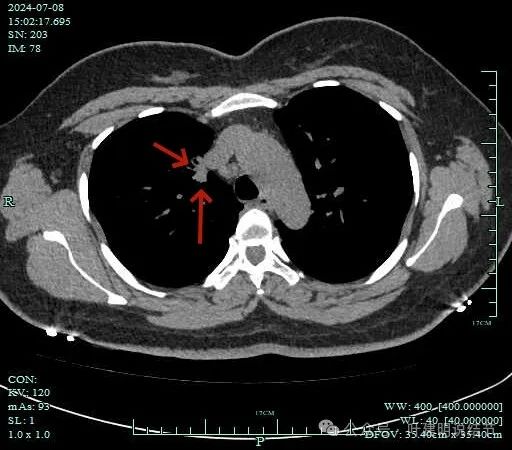

再看2024年7月份的影像:

表面不平,软组织密度。

灶边部分细支气管扩张,腔静脉旁淋巴结较大

病灶有血管与之相连,淋巴结更显得明显了。